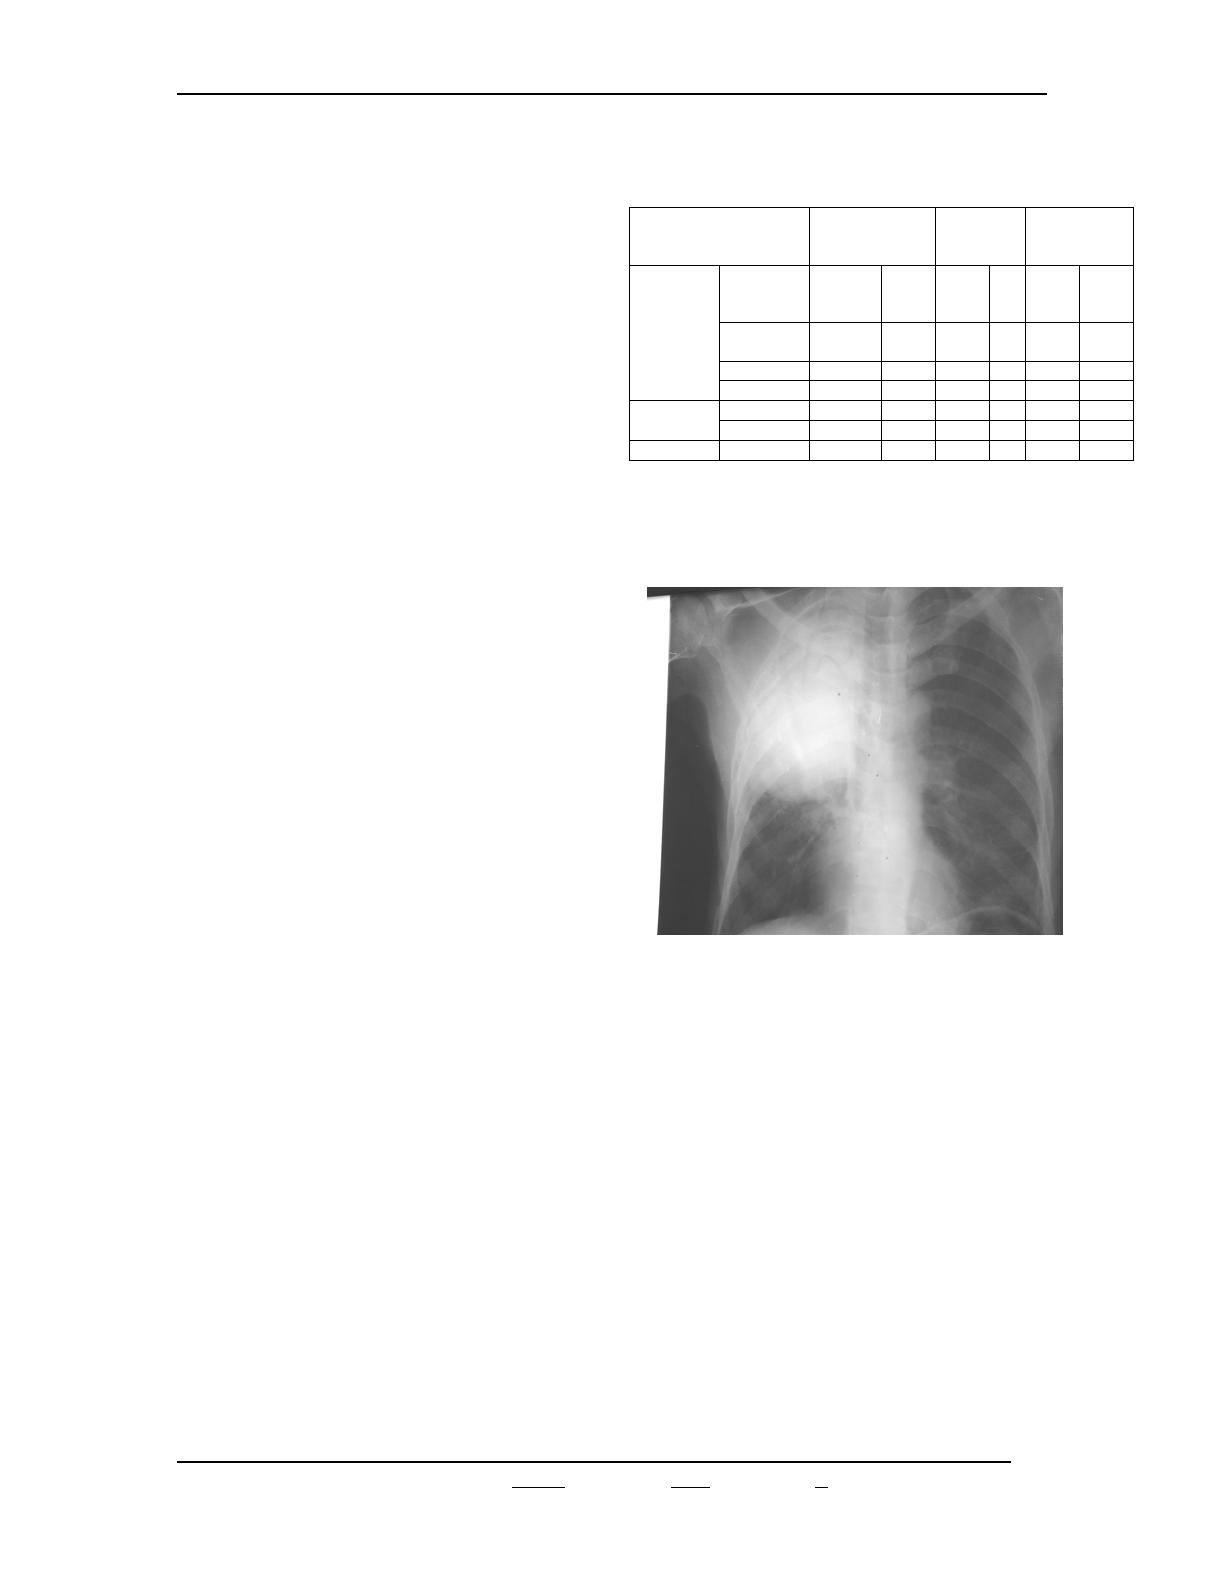

(p=0,7).Sur le plan radiologique, l’atteinte du

lobe supérieur droit a été retrouvée dans

67,8 % sans différence selon la sérologie VIH

(p=0,9). Il s’agissait d’opacité systématisée

non excavée (figure1) et d’opacité

systématisée excavée. Chez les patients

présentant une excavation, la

symptomatologie évoluait depuis au moins 3

semaines. Le tableau I présente la

répartition des patients selon l’aspect

radiologique et la sérologie VIH. Il faut noter

qu’un patient séropositif et un patient

séronégatif ont présenté chacun une

pneumonie bilatérale des lobes supérieurs.